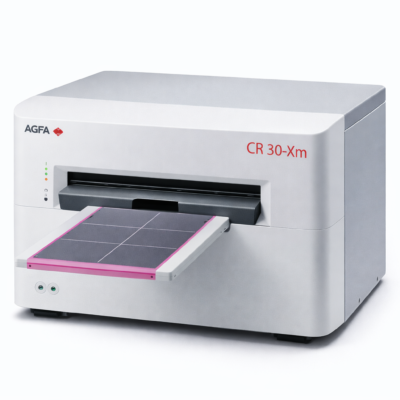

🔹 Détecteur Sans Fil Haute Définition

-

Format : 43 x 43 cm

-

Profondeur de gris 16 bits

-

Reproduction précise des détails

-

Batterie amovible + batterie de secours

Option disponible :

📏 25 x 30 cm (10 x 12 pouces) pour incubateurs et néonatalogie.